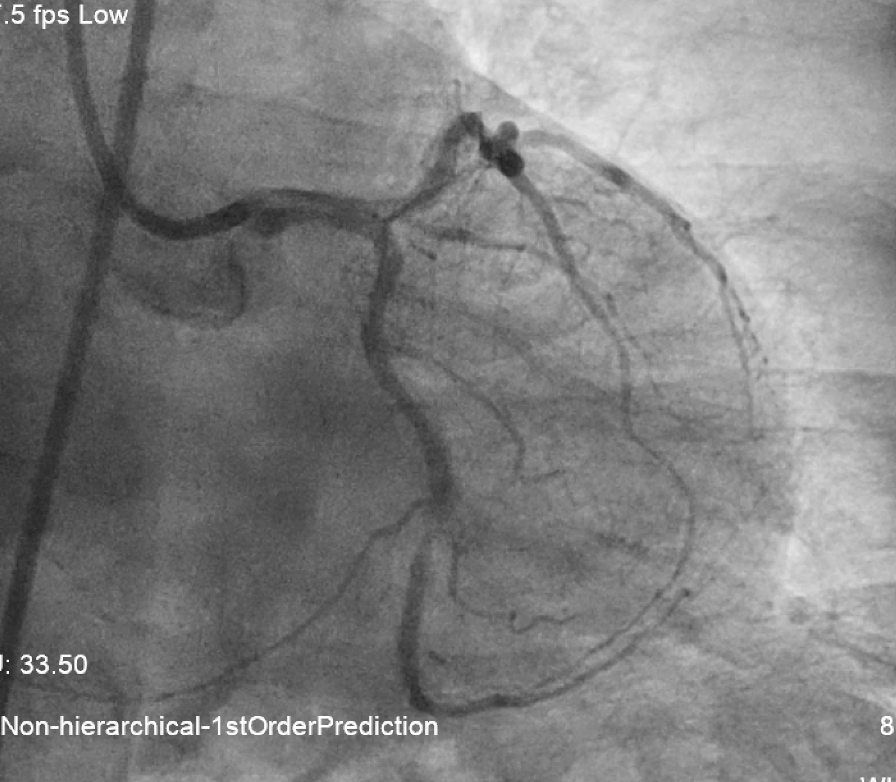

•Very calcified vessels •LM: diffuse disease •LAD: pLAD and mLAD severe stenosis •LCx: mLCx critical stenosis •RCA: dominant, mRCA critical lesion

L system coro 2.mov

L system coro 1.mov